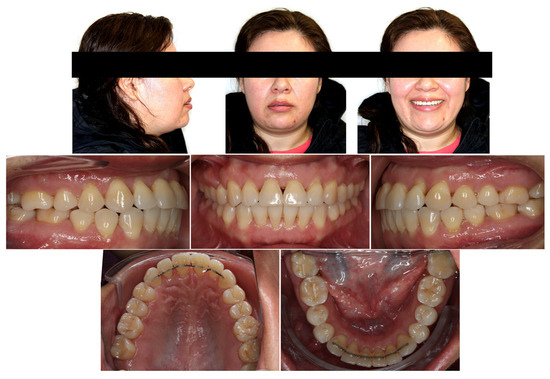

3. Treatment Results